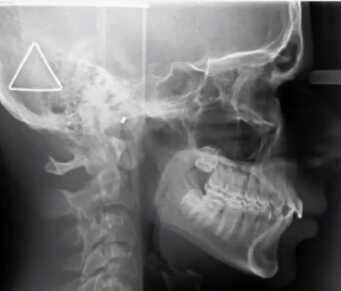

While obstructive sleep apnea is commonly associated with adults, it is important to recognize that children can also be affected by this condition. Pediatric obstructive sleep apnea refers to a sleep disorder in which a child’s breathing is partially or completely obstructed during sleep, leading to disrupted breathing patterns and inadequate rest. The underlying cause of this condition is often the narrowing or blockage of the upper airway during sleep.

Enlarged tonsils or adenoids are frequent culprits of obstructive sleep apnea in children. However, other factors, such as genetic predisposition, nasal allergies, Down syndrome or cerebral palsy, may also increase the risk of pediatric sleep apnea.

The treatment our dentist recommends for your child’s pediatric sleep apnea will depend on various factors, including the child’s symptoms, age, overall health and the severity of the condition. We may recommend myofunctional therapy involving mouth and throat exercises or Vivos sleep apnea treatment.